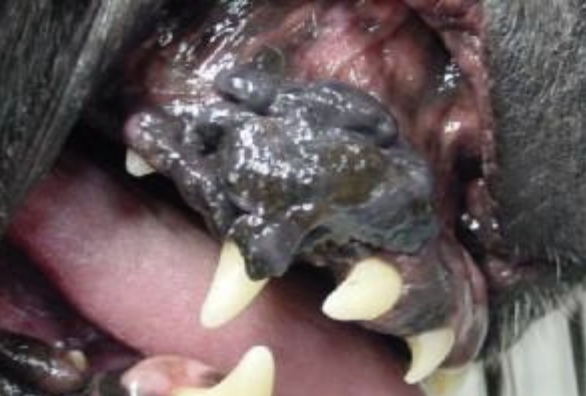

Benign Oral Neoplasia

Papillomas-pale colored cauliflower like growths, viral

slow growing but may be locally invasive